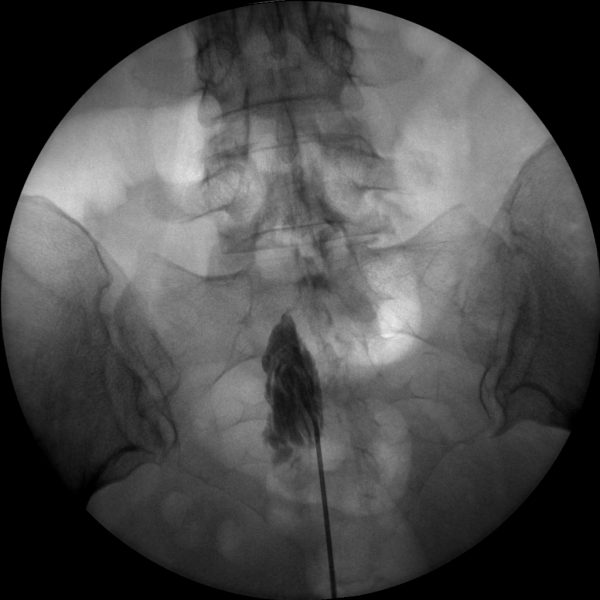

The high-resolution 1kx1k images from Skan-C helps pain management professionals visualize the position of the needle in relation to the epidural space, ensuring accurate and effective treatment.

Skan-C is an invaluable tool for performing Radiofrequency Ablation (RFA), a procedure that uses heat to disable nerves responsible for transmitting pain signals. Skan-C's advanced imaging capabilities facilitate precise localization of the target nerves, guiding the placement of the RFA needle electrode accurately.

Skan-C is well-suited for performing Spinal Cord Stimulation (SCS), a pain management technique that involves implanting a device to deliver electrical impulses to the spinal cord, altering or blocking pain signals. Skan-C's high-resolution imaging assists pain management professionals in placing the leads precisely and evaluating their position to the spinal cord.